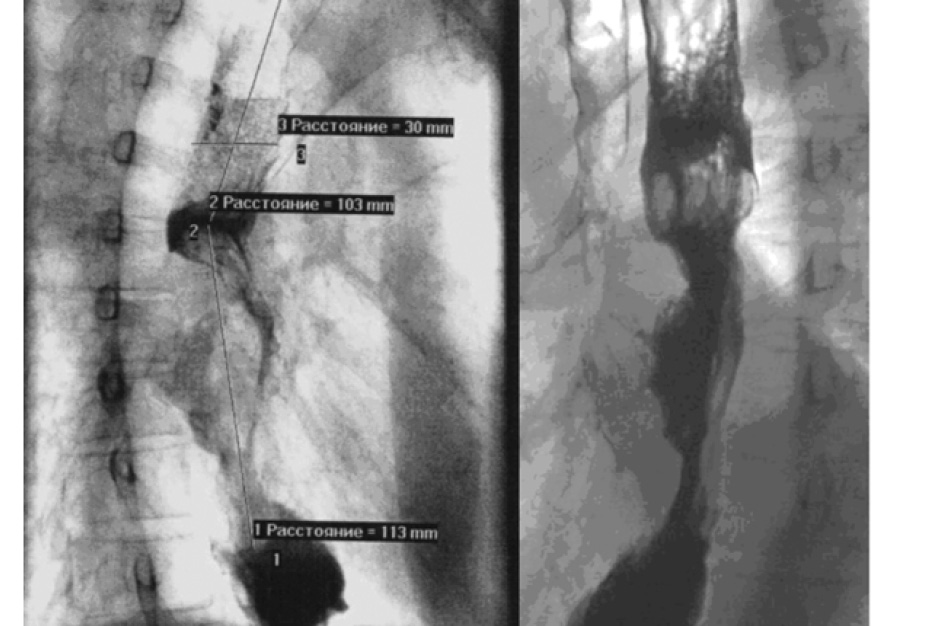

На кафедре общей хирургии Военно-медицинской академии имени С. М. Кирова проведено эндоскопическое стентирование пищевода 78 пациентам, проходившим лечение в период с 2007 по 2020 г. по поводу опухолевого поражения пищевода и кардиального отдела желудка, и 2 пациентам с рубцовой стриктурой пищевода. Группа пациентов включала в себя 61 мужчины и 19 женщин, средний возраст которых составил 64,2 ± 8,6 года. 69 больных имели на момент обращения признаки дисфагии III–IV степени, у 6 выявлен трахео-пищеводный и у 3 — пищеводно-плевральный свищи, образовавшиеся при опухолевом распаде. По данным клинико-инструментальных методов обследования всем онкологическим пациентам установлена IV стадия заболевания с поражением внутригрудных лимфатических узлов, наличием отдаленных метастазов и признаками дисфагии III–IV степени. Такой категории пациентов не показано радикальное хирургическое вмешательство, а циторедуктивные вмешательства операции сопровождаются высоким риском развития осложнений и летального исхода. Основным методом устранения синдрома дисфагии у таких пациентов стало эндоскопическое стентирование пищевода с целью восстановления проходимости пищевода. Длительное поддержание просвета пищевода позволяет поддержать метаболизм организма за счет адекватного естественного поступления питательных веществ, продлить и улучшить качества жизни больного. Диагностика заболевания включала упорядоченный нами алгоритм обследования. Первым этапом проводилось исследование обязательных параметров крови и мочи, рентгенография грудной клетки и брюшной полости, УЗИ, проводилась КТ живота и груди, сцинтиграфия. Также неотъемлемую роль носило рентгенконтрастное и эндоскопическое исследование пищевода, что позволяло определить протяженность, характер и степень сужения. Для гистологической верификации выполнялась биопсия области опухолевого роста, в 77% выявлена аденокарцинома с различной степенью дифференцировки, а в 23% — плоскоклеточный рак. Морфологическая характеристика опухоли не влияла на выбор и тактику паллиативного лечения. После подтверждения и постановки окончательного диагноза проводился подбор необходимого стента по имеющимся параметрам протяженности опухоли и степени сужения просвета пищевода. Для эндоскопического стентирования пищевода мы использовали стенты фирмы «M. I. Tech» (Seoul, Korea), одобренные для применения в клинической практике во всем мировом эндоскопическом сообществе. Отличительными особенностями модельного ряда стентов является наличие покрытия, которое устраняет возможность диффузного прорастания стента, а также наличие рентгенконтрастных меток для удобства контроля положения. Установка производилась короткими эндоскопическими системами доставки малого диаметра по заранее заведенному жесткому проводнику. Для проведения стентирования минимальный диаметр просвета пищевода должен был составлять 6–8 мм. При невозможности проведения системы доставки за опухолевый стеноз, проводили эндоскопическое бужирование, либо баллонную дилатацию до нужных размеров. В случае дисфагии IV степени возникала необходимость в деструкции опухоли, которая осуществлялась использованием аргоноплазменной коагуляции. На этапах освоения методики мы отдавали предпочтение комбинированному рентгеноэндоскопическому методу установки стента. Под эндоскопическим и рентгеноскопическим контролем стент устанавливался на уровне стриктуры, таким образом, чтобы проксимальный конец стента выходил на большое расстояние за зону опухолевого сужения, чем на дистальном конце (рис. 1).

Рис. 1. Эндоскопический и рентгенологический контроль этапа проведения стента и этапа высвобождения стента

В дальнейшем от этой методики отказались и все манипуляции проводились под эндоскопическим контролем с последующим рентгенографическим исследованием, что способствовало снижению уровня воздействия излучения, как на больного, так и на персонал. Все вмешательства осуществлялись под внутривенной анестезией. Адекватное расправление стента, удовлетворительная оценка стояния стента, отсутствие смещения были показанием для начала перорального приема пищи.